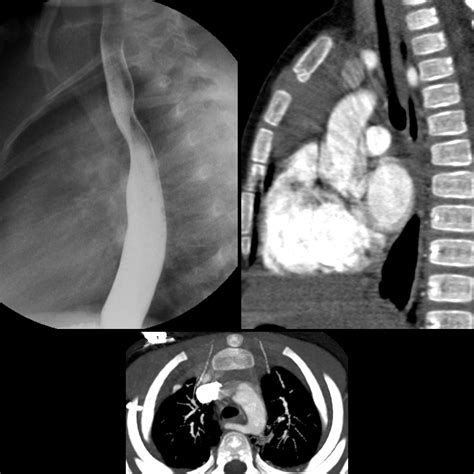

• Barium Swallow: Can demonstrate an indentation on the posterior wall of the esophagus, suggestive of an aberrant vessel.

• Computed Tomography Angiography (CTA): Provides detailed images of the aortic arch and its branches, confirming the diagnosis and defining the course of the aberrant artery.

A 45-year-old woman presented for a routine health check-up. A chest X-ray revealed an abnormal aortic arch contour. Further evaluation with CTA confirmed the presence of an Aberrant Right Subclavian Artery with a retroesophageal course. The patient was asymptomatic and underwent regular follow-up without any intervention.

Case Study 2: Symptomatic ARSA

A 30-year-old man presented with a history of dysphagia and chest pain. A barium swallow demonstrated an indentation on the posterior wall of the esophagus. CTA confirmed the presence of an Aberrant Right Subclavian Artery with a retroesophageal course. The patient underwent surgical division and reimplantation of the aberrant artery, with significant improvement in symptoms post-operatively.